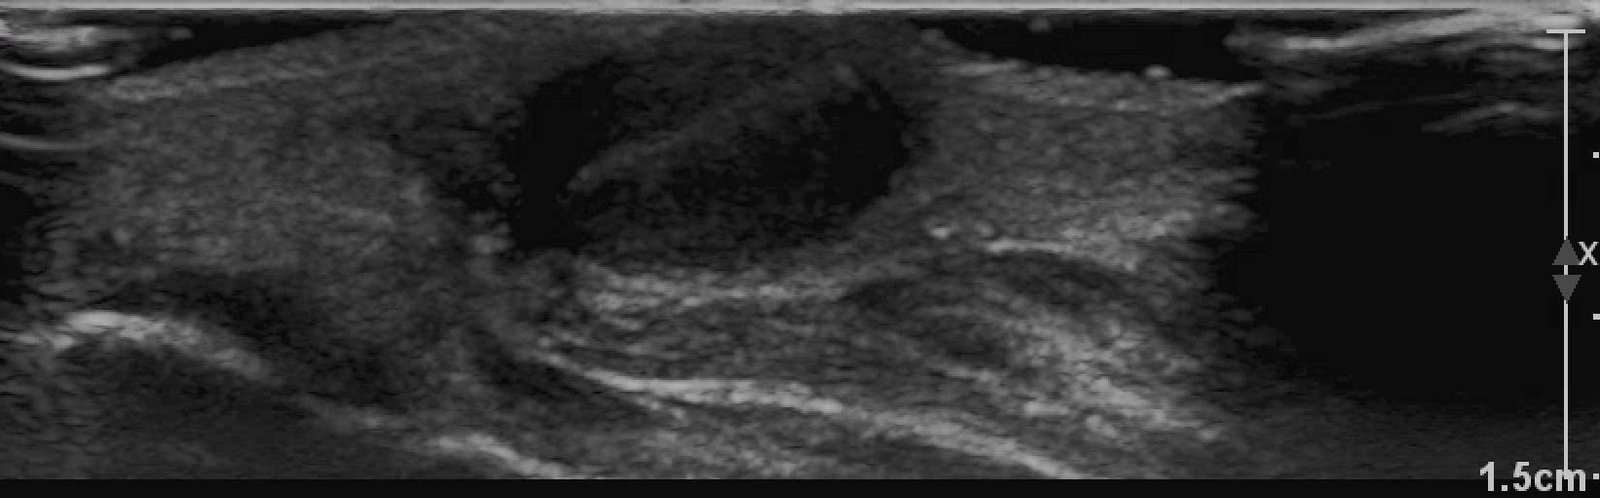

X-rays of the foot were obtained and no radiopaque foreign body was visualized. Due to high clinical suspicion for retained foreign body, a point-of-care ultrasound was performed by applying a high-frequency linear probe at the area of discomfort. In the long axis an ovoid focus of hypoechogenicity (orange outline) is visualized. Within this finding there is a linear focus (yellow line) of increased echogenicity measuring 1 mm in diameter and 1 cm in length. On short axis view, a rectangle focus (green dot) demonstrating shadowing (blue highlight) is seen.